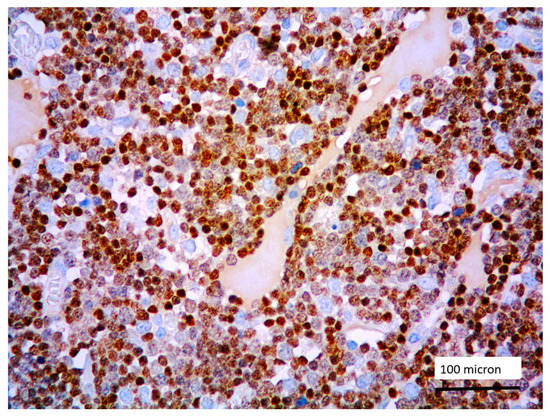

In all the cases, the lymph node histology and immunohistochemical profile were consistent with T-LBL diagnosis. The nodal architecture was effaced by a diffuse proliferation of medium-sized cells with dispersed chromatin and scarce cytoplasm (Figure 1) with high proliferative fraction and usually positive for TdT (Figure 2), CD1a and T-cell markers such as CD3 (Figure 3), CD2, CD8, CD5, CD7. B-cell markers (CD79α, CD20, PAX5 and CD22) were mostly negative; a weak CD79α co-expression was noted in 2/11 cases; myeloid (MPO, CD117, CD68KP1) and monocytic (CD68PGM1) markers were negative. In 5/11 cases, a minor component of immature myeloid cells was identified (Figure 4). Aggregates of mature eosinophils (Figure 5) admixed to the lymphoblastic proliferation were noted in 5/11 cases, whereas clusters of proerytroblasts (Figure 6 and Figure 7) were identified within T-LBL in 1/11 cases. Unexpectedly, LMO2 immunostaining was found to be negative in 9/11 T-LBLs (Figure 8); in the remaining 2 cases, LMO2 was partially expressed (less than 30% of cells) with either moderate or low degree of intensity, respectively (Figure 9).

Figure 1. T-LBL medium-sized cells with high nuclear-cytoplasmic ratio and dispersed chromatin (case 5, Giemsa staining, magnification 400×).

Figure 2. Lymphoblastic proliferation diffusely expressing TdT (case 5, magnification 400×).